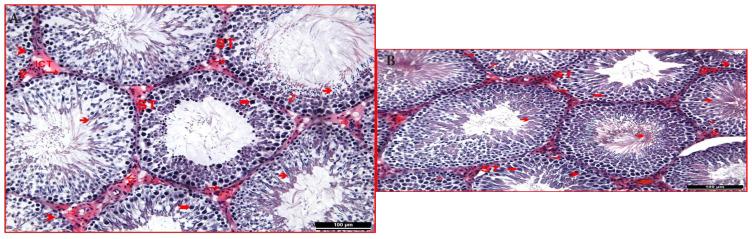

Thirty-six male Wistar Albino rats were used and separated into six groups: i. Control; ii. Sham; iii. RFR exposure; iv. Control-melatonin; v. Sham-melatonin; vi. Melatonin + RFR exposure. Animals were exposed to 2600 MHz RFR with electric (E) field levels of 21.74 V/m for 30 min per day, 5 days per week, for 4 weeks. All testicular tissue samples were evaluated under a light microscope for hematoxylin-eosin staining. Biochemical analyses were performed by measuring malondialdehyde, total nitric oxide, glutathione, and glutathione peroxidase levels. We evaluated the combined effects of prolonged RFR exposure and melatonin treatment on ROS-mediated structural changes in testicular tissues.

Results showed that reactive intermediates (malondialdehyde and total nitric oxide) increased significantly with RFR exposure, while the protective effect of melatonin effectively reduced the radical levels of the tissues. Histological evaluation revealed a decrease in cell population and connective tissue elements under RFR exposure, accompanied by marked edema in the testicular tissues.